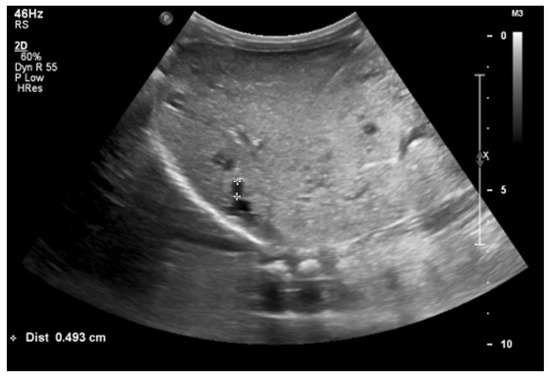

At 4 months of age, the boy was admitted to the hospital due to a hypertensive crisis (BP 162/128 mmHg). Chest X-ray demonstrated cardiomegaly, and echocardiography (ECHO) showed a significant left ventricular hypertrophy and impaired contractility. Abdominal US detected increased kidneys length (right: 101 mm (z-score 8.72); left: 90 mm (z-score 6.59)), with increased echogenicity and loss of corticomedullary differentiation, as well as numerous cysts 5–6 mm in diameter. The liver was enlarged with increased echogenicity with cysts 6–8 mm in diameter (Figure 1 and Figure 2). Doppler US demonstrated high-resistance intrarenal blood flow (RI: 0.75–0.84). Laboratory tests showed microcytic anemia, renal function was assessed as serum creatinine, the glomerular filtration rate (GFR) was estimated according to the Schwartz formula, and liver function was all normal. The boy received multi-drug therapy to control hypertension and heart failure. ECHO, performed after 6 months, was correct.

Figure 2. Ultrasonography of the liver at the age of four months (hyperechogenic, enlarged liver with multiple cysts).